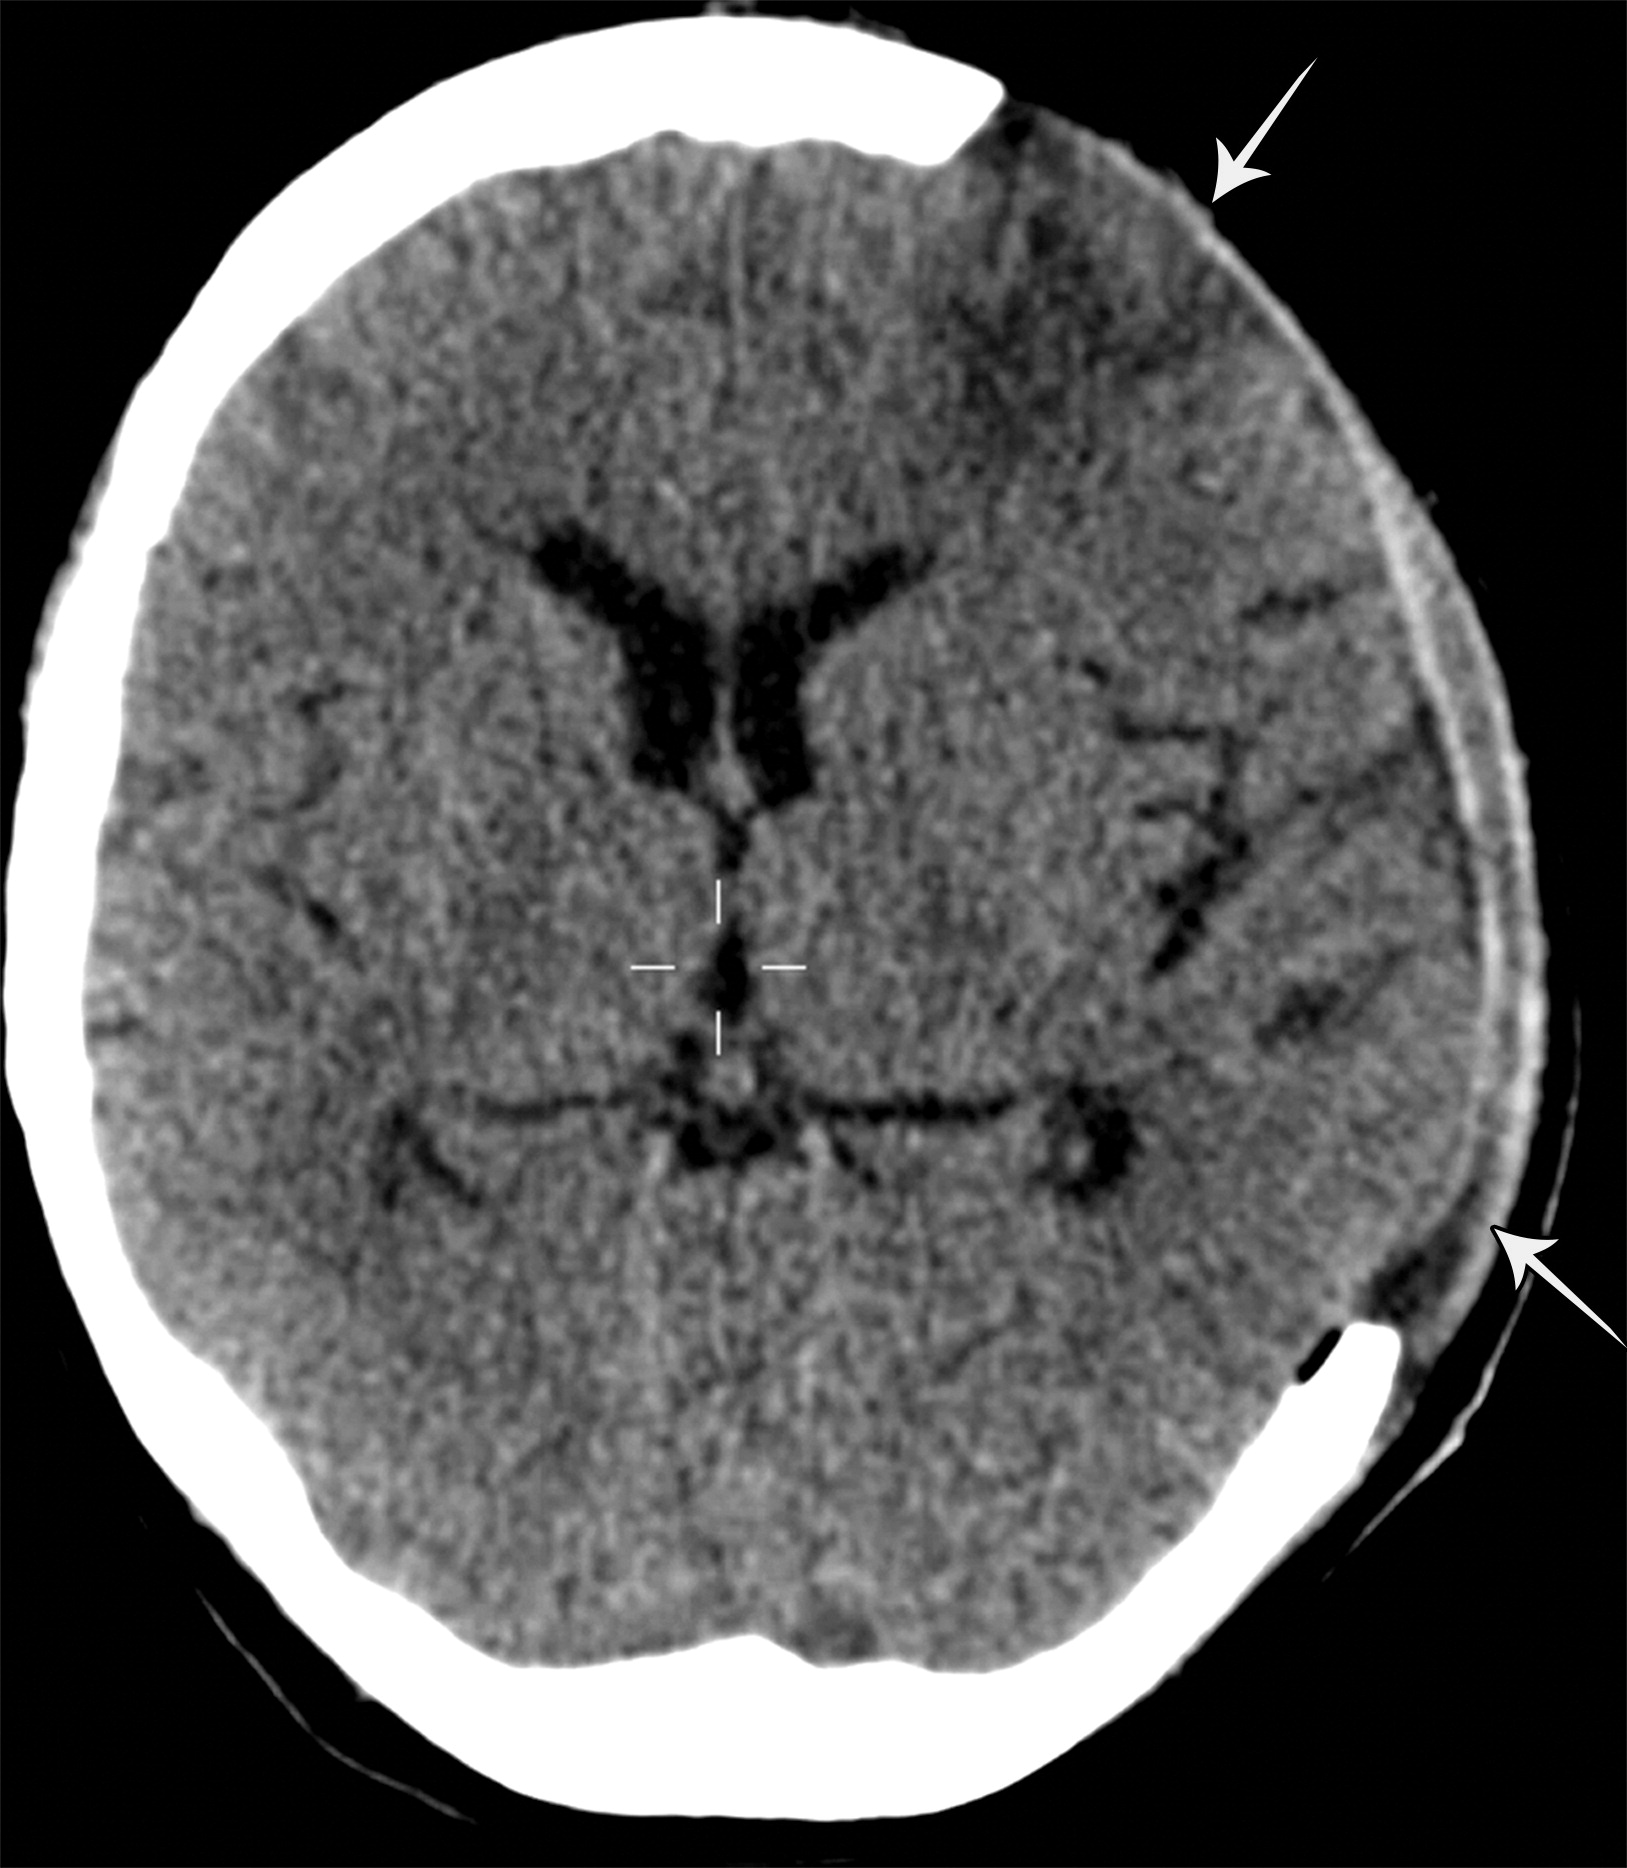

13f0c419b13c075af8c7957aee746573.jpeg

颅外脑疝。左侧额叶的急性梗死,注意右侧小灶状病变(白色短箭头)。数天后,患者出现血管源性脑水肿,并进行了去骨瓣减压术。

811f47e33d6b1d13943a77f716f35d33.jpeg

颅外脑疝。去骨瓣减压术后,脑实质从左侧额颞部缺损的位置疝出(白色长箭头)。大脑侧裂增大,左侧侧脑室的额角及枕角回缩。